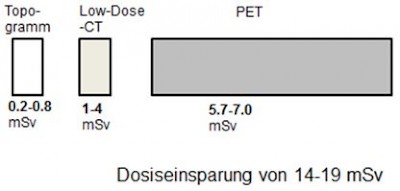

Überlegungen zur Reduzierung der Strahlenexposition:

Falls im Vorfeld der PET-CT Untersuchung eine CT-Schnittbilddiagnostik gelaufen ist, kann man auf das diagnostische CT bei der PET-Untersuchung verzichten. Die Low-Dose CT reicht völlig aus, um die PET-Bilder zu anatomischen Strukturen zuzuordnen.

Falls ein diagnostisches CT bei der PET-Untersuchung notwendig ist, kann man auf das Low-Dose CT verzichten, und das diagnostische CT zur Schwächungskorrektur heranziehen.